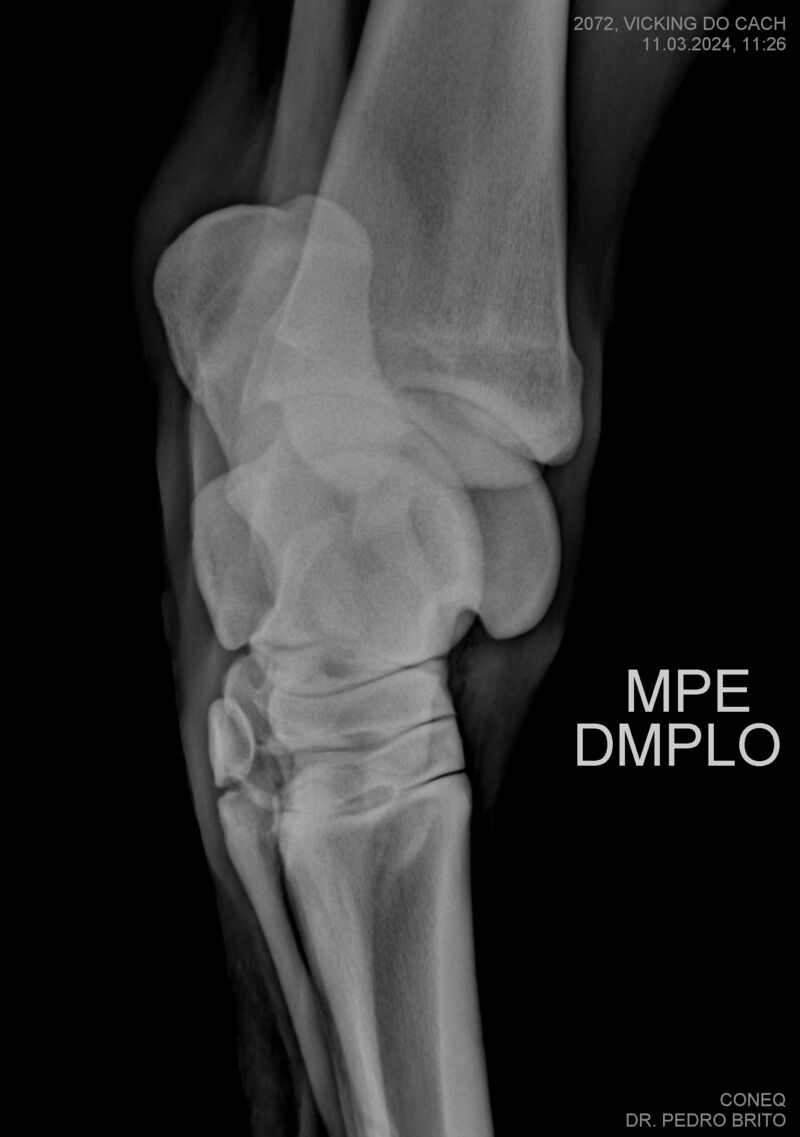

VIKING DO CACH